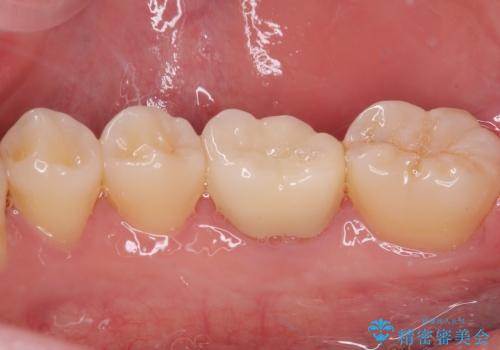

まずはしみる上顎の歯を仮歯に置き換え、その後下顎の根管治療を行った上で、異常が認められなければオールセラミッククラウンにて補綴治療を行うこととしました。

上顎は仮歯に置き換えた後に、それまでの痛みは一切感じなくなり、下顎も一度目の根管治療で痛みを感じることはなくなりました。

根管治療を行った歯の周辺にある病変は数ヶ月後にレントゲン写真を撮って確認する必要があるため、今後経過観察を行っていく予定です。